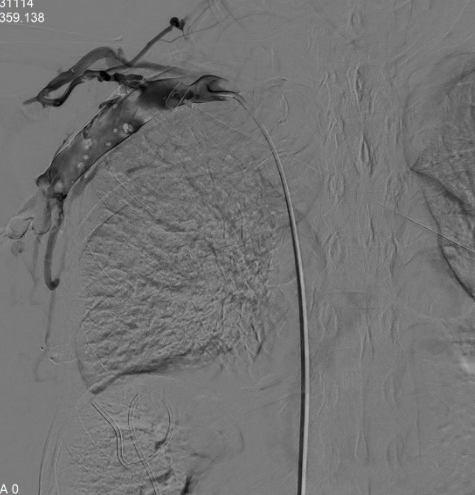

經(jīng)過測量確定優(yōu)先使用球囊進行狹窄段靜脈預(yù)擴張,在韋運豪主治醫(yī)師、熊偉主治醫(yī)師及朱海副主任醫(yī)師的合作下對閉塞段血管反復(fù)擴張數(shù)次,再次造影見閉塞段血管較前改善,但靶血管區(qū)狹窄程度仍約80%,根據(jù)國內(nèi)外專家指南共識,當經(jīng)皮腔內(nèi)血管成形術(shù)(PTA)后閉塞血管段發(fā)生彈性回縮或殘余狹窄>30%時,具有進一步行支架置入術(shù)干預(yù)的指征。

DSA引導(dǎo)下精準定位釋放支架成功,再次造影,頭臂靜脈閉塞段開通,血流可順利回流至上腔靜脈,但右側(cè)鎖骨下靜脈遠心端及腋靜脈可見血栓形成,遂予以留置導(dǎo)管溶栓治療。